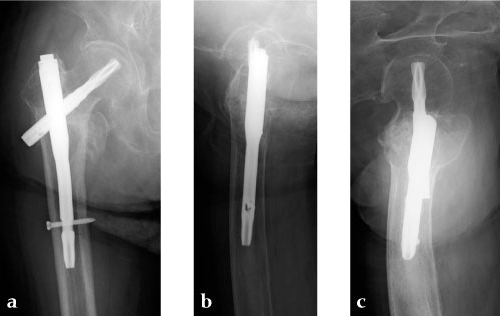

A 78-year-old Japanese patient fell while at her home and sustained an AO 31-A2.1 injury (see Fig 5).

She was operated on the next day and fixed with a PFNA Asia (size: extra small, angle 130 degrees, distal diameter: 9 mm, blade length 100 mm) (Fig 6a). Good reduction and stable fixation were obtained. Full weight-bearing gait was allowed on the second postoperative day. There was an uneventful postoperative course, and good union was obtained at three months after surgery (Fig 6b).